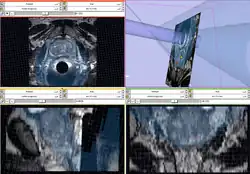

ProstateNav Module for MRI guided robot assisted biopsy of the prostate.

ProstateNav Module for MRI guided robot assisted biopsy of the prostate. -